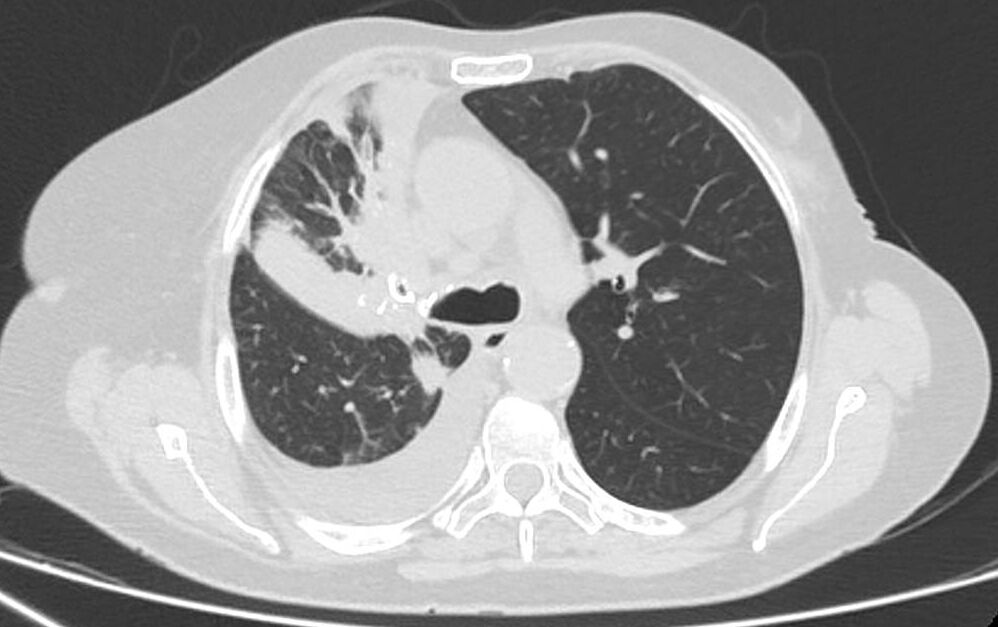

O cirurgião torácico é o especialista mais habilitado para o diagnóstico das patologias dos pulmões. Com a crescente incidência de Câncer pulmonar mesmo em paciente não fumantes, cada vez mais jovens, casos que a detecção precoce é importantíssima.

A avaliação dos nódulos pulmonares deve ser feita por médico experiente e capacitado para a correta condução com tratamento individualizado.